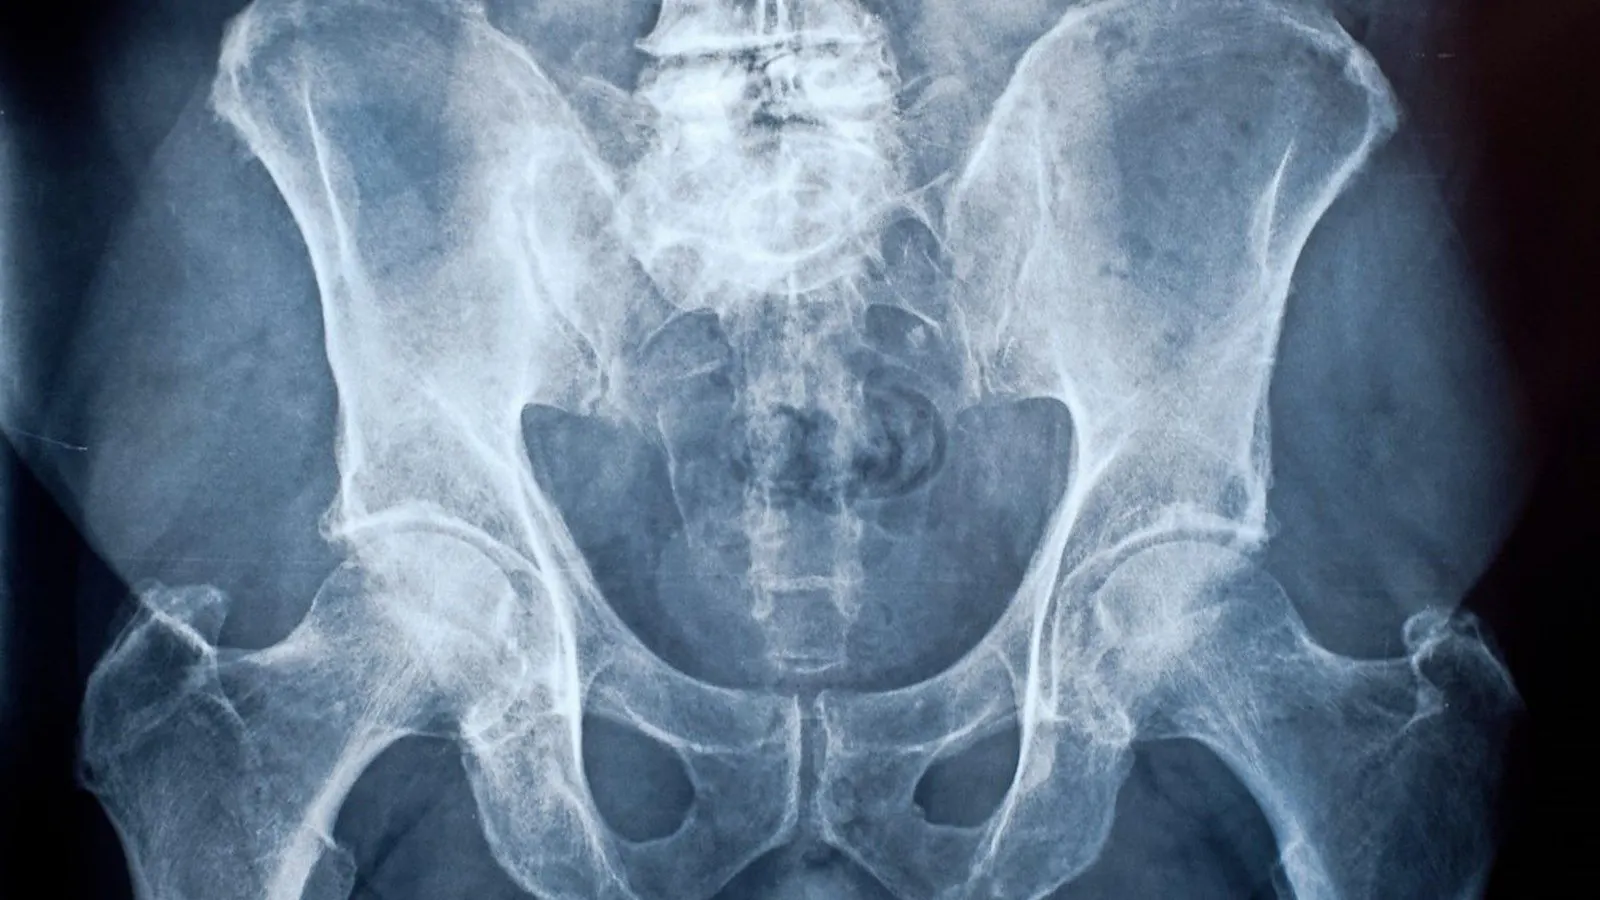

Knochensarkome treten recht häufig bei Kindern auf

Auch wenn Sarkome selten sind: Bei Kindern und Jugendlichen zählen Knochensarkome mit einem Anteil von zwölf bis 15 Prozent zu den häufigsten Krebserkrankungen. Bei älteren Patienten überwiegen dagegen die Weichgewebesarkome. Sie stellen in Deutschland bis zu 4000 der jährlich knapp 5000 Sarkom-Neudiagnosen.